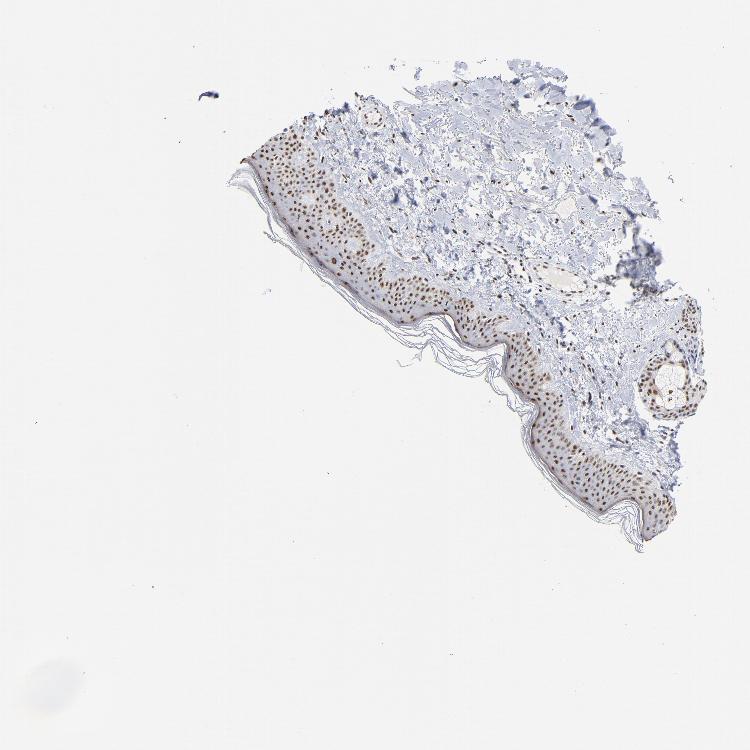

SKIN 1 - Antibody stainingi

Antibody staining in the annotated cell types in the current human tissue is reported as not detected, low, medium, or high, based on conventional immunohistochemistry profiling in selected tissues. This score is based on the combination of the staining intensity and fraction of stained cells.

Each image is clickable and will lead to virtual microscopy that enables deeper exploration of all samples and also displays staining intensity scores, fraction scores and subcellular localization as well as patient and tissue information for each sample.

Antibody HPA002031

Langerhans High

Fibroblasts High

Keratinocytes High

Melanocytes High

SKIN 2 - Antibody stainingi

Epidermal cells Medium